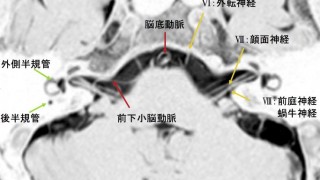

小脳橋角部の正常解剖 MRI CISS画像より

小脳橋角部というのは、聴神経腫瘍が出来やすい部位で頭部MRIのチェックポイントの1つです。以前は内耳道内腫瘍などは造影MRIを使って腫瘍を確...